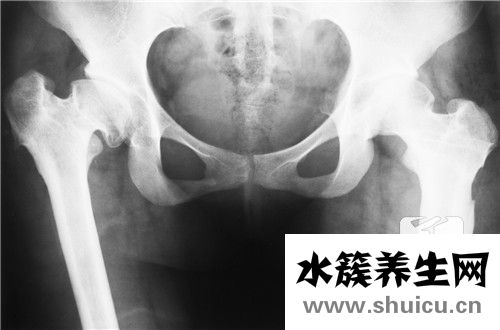

雙側(cè)骶髂關(guān)節(jié)炎是遺傳病。年齡越大越容易發(fā)展,男性患者總數(shù)遠遠高于女性患者。疾病的原因尚未確定。大部分患者臀部有疼痛,這種疼痛的抗壓強度比較高。如果生病了,可以考慮熱敷或者吃藥緩解。其次,如果比較嚴重,需要考慮醫(yī)院。醫(yī)生看了都有可能吃藥,針灸或者中醫(yī)按摩。

骶髂關(guān)節(jié)炎是關(guān)節(jié)炎中的骨關(guān)節(jié)炎的一種支系。大部分的骶髂關(guān)節(jié)炎并并不是獨立的一個病癥,只是由別的病癥造成的,如很多強直性脊椎炎炎的病人在病發(fā)前期主要表現(xiàn)為骶髂關(guān)節(jié)炎,因此 確診出骶髂關(guān)節(jié)炎還是不足的,應(yīng)進一步查驗是哪種原因造成的。

雙側(cè)骶髂關(guān)節(jié)炎關(guān)鍵的臨床癥狀主要表現(xiàn)為骶髂關(guān)節(jié)位置的疼痛病癥,尤其是在疲勞或是著涼的狀況下,疼痛會更為強烈,比較嚴重的可能會影響到一切正常活動。這就是雙側(cè)骶髂關(guān)節(jié)炎的臨床表現(xiàn)。